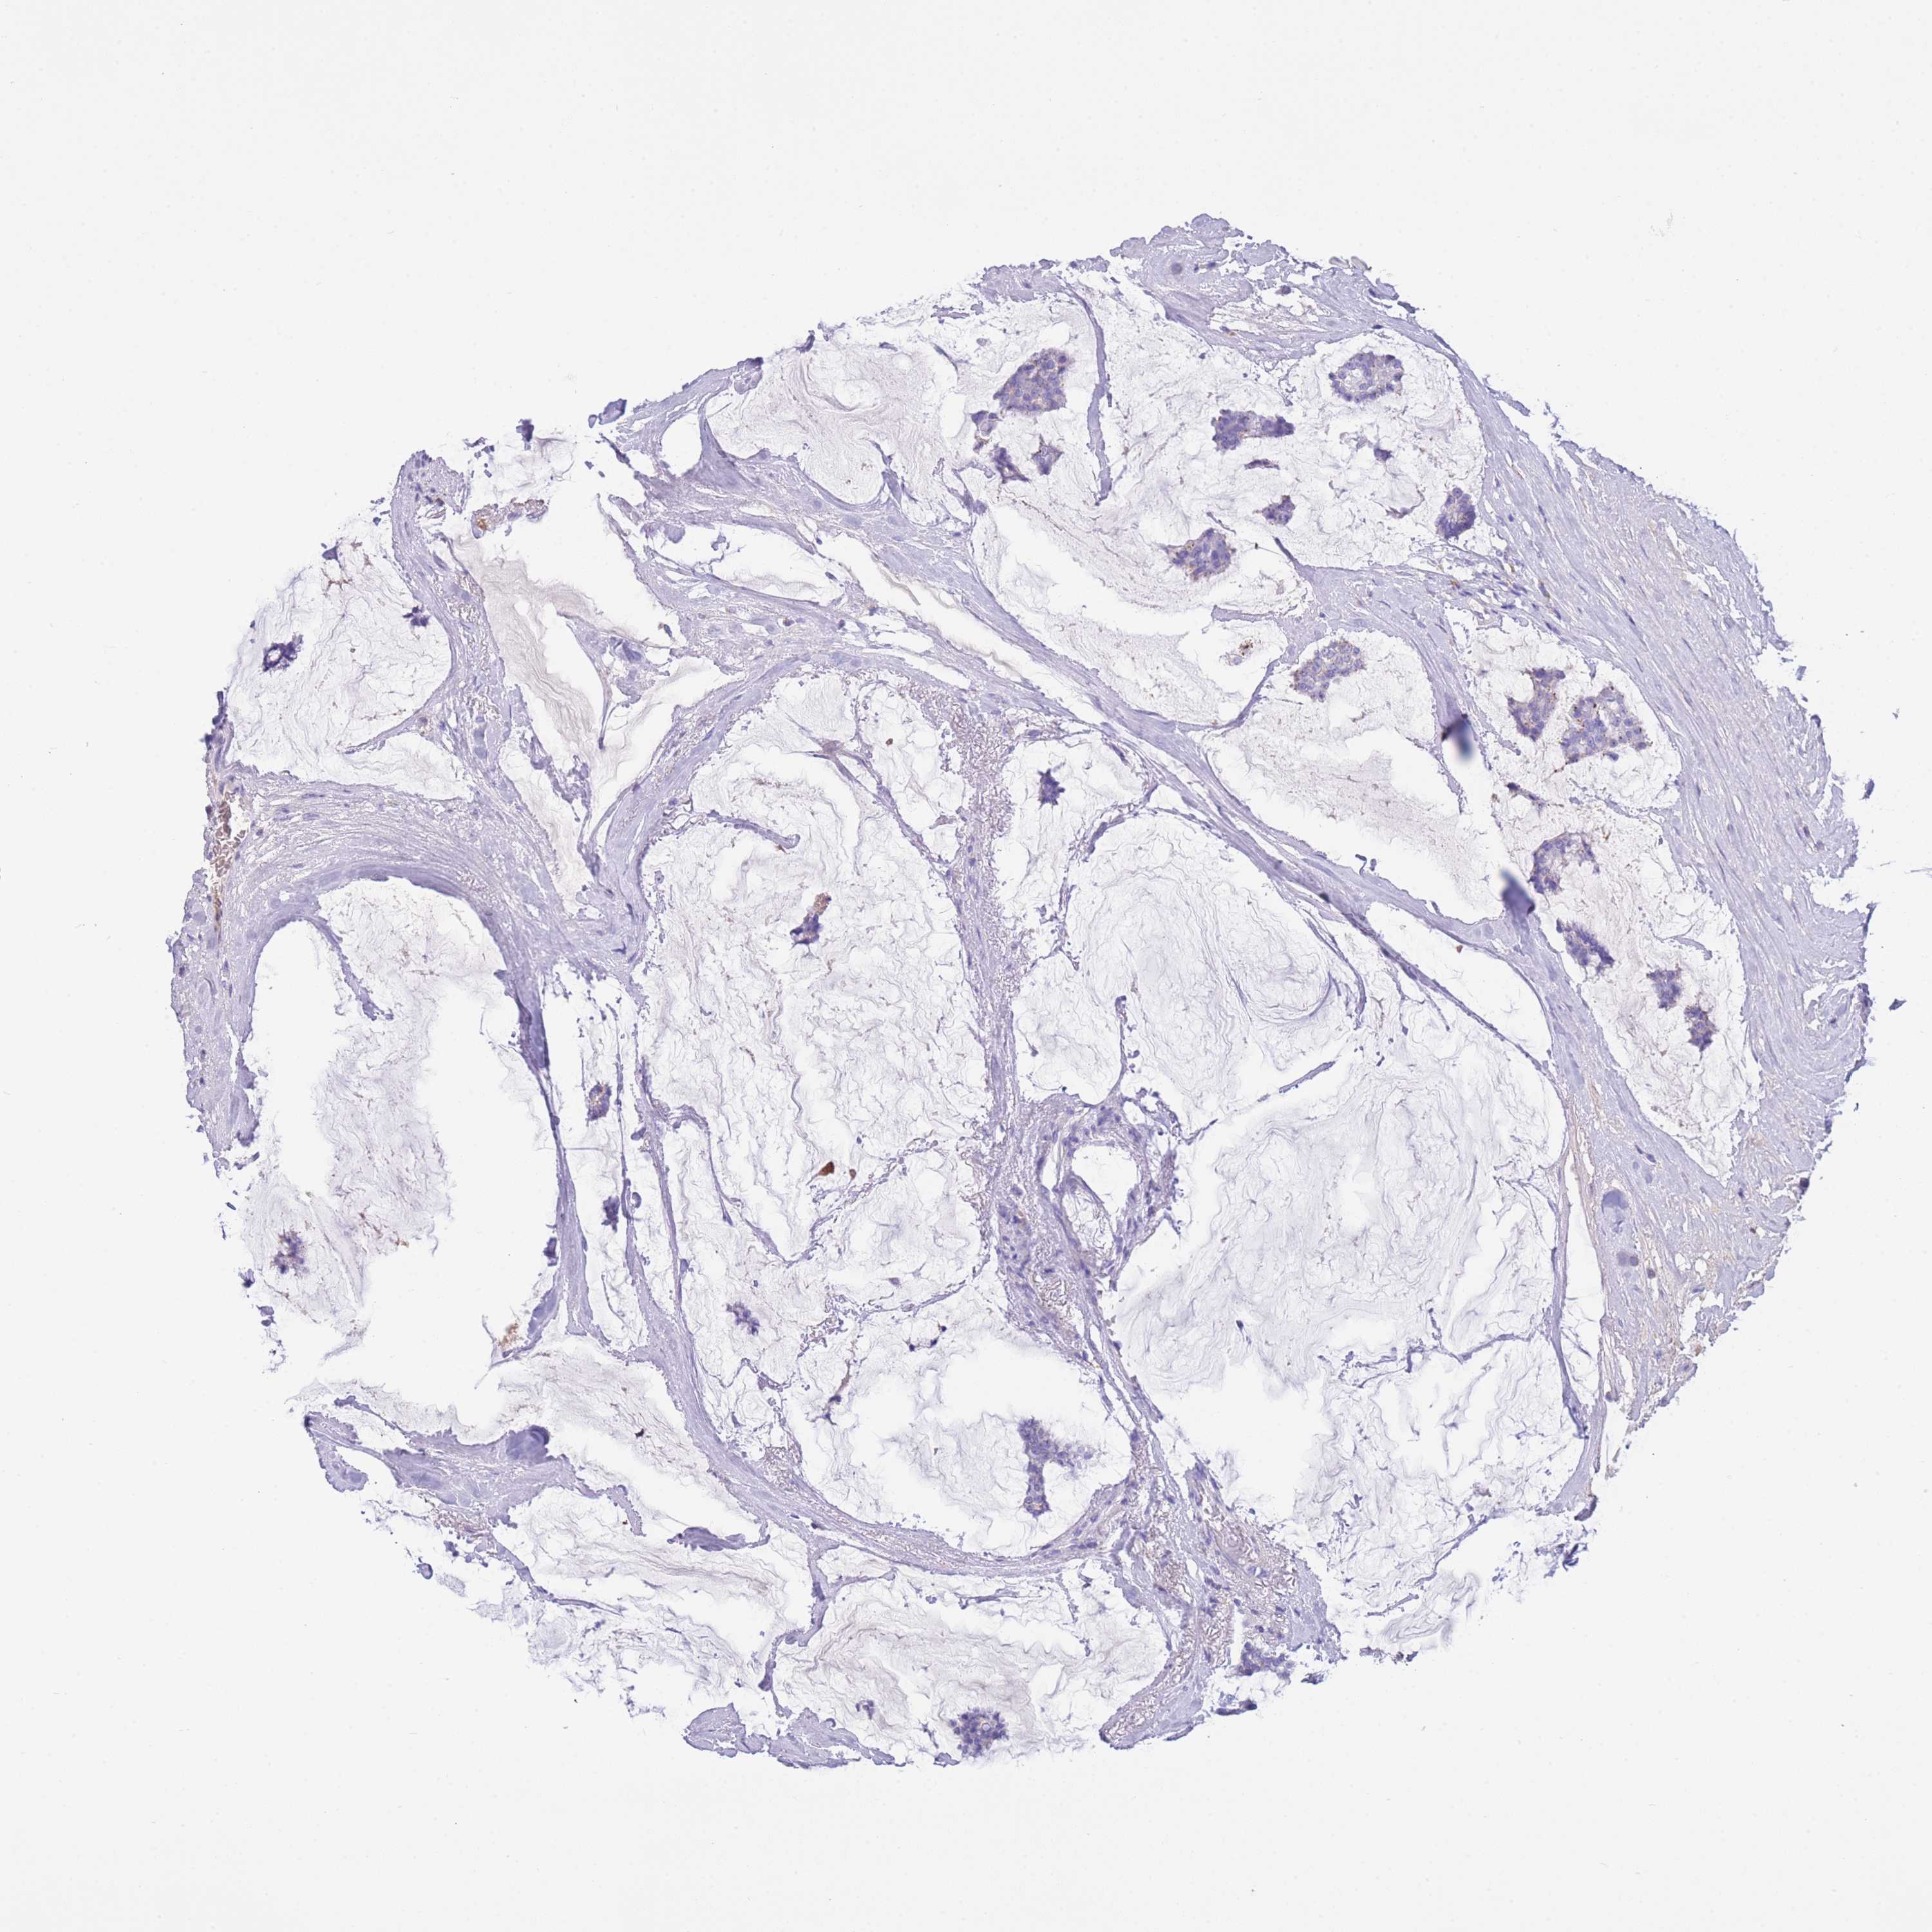

CANCER BREAST CANCER Show tissue menu

BRCA TCGA BRCA VALIDATION PROTEIN EXPRESSION